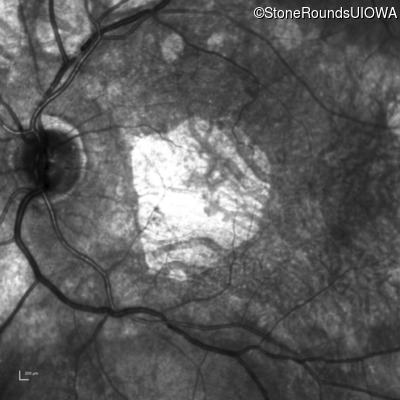

Infrared Fundus Photograph - Right - 20/100

Exemplar